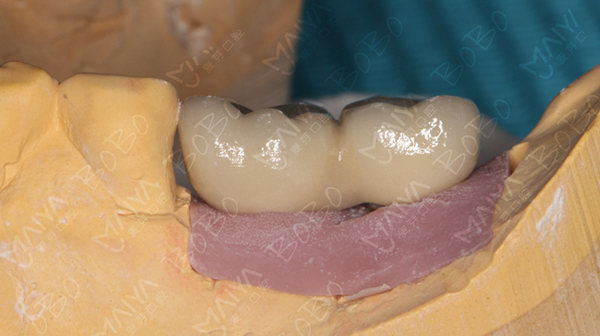

术前模拟种植牙

种植完成后的牙齿情况